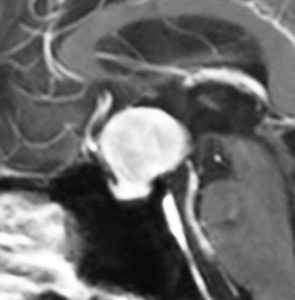

40代の女性に,軽度の両耳側半盲で発生したものです。視交叉と視床下部の下面に腫瘍があり,下垂体柄の位置が全くわからず,下垂体の前葉と後葉は侵されていません。ですから,下垂体柄から発生した腫瘍であり,pituicytomaが強く疑われます。T2ではほぼ等信号,小さなのう胞があり,ガドリニウムで強く増強されます。手術では正常下垂体柄の一部が右側にうすく残っており,幸運にも亜全摘出できて下垂体機能は温存できました。残存腫瘍は増大傾向を示していません。でも,このようなタイプを積極的に摘出すると,汎下垂体機能低下症を招くことが多いので,手術するかどうかの判断はとても難しいです。